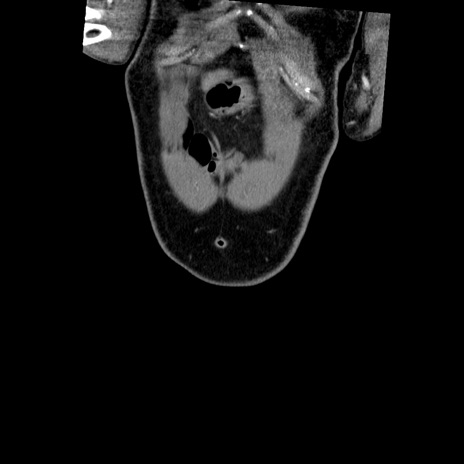

横断像